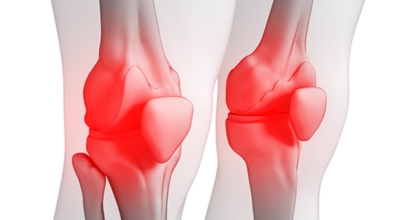

2. 콘드로이친 효능 - 관절 건강

콘드로이친의 가장 가장 저명한 효능 중 한 종류로 관절 건강이 있답니다. 연골이 마모되면서 뼈와 뼈 사이가 좁아져 관절염이 발생하고 통증이 발생되는데 콘드로이친을 먹게 되면 관절염 보완에 도움이 돼요. 마모되어 얇고 연약해진 연골의 내마모성과 볼륨 유지를 이완하여주는 구실을 해서 연골을 지켜주며 염증이 생기게 될 수 있는 관절에 쿠션을 제공해서 통증을 떨어뜨리고 일상생활을 원활하게 하도록 하는데 보탬이 돼요. 콘드로이친을 연속적으로 먹게 되면 관절 건강에 좋습니다.

관절염은 염증과 관련되어 있는 질환인 만큼 관절 보호도 중요하는데, 염증을 제한하는 것도 중요합니다. 콘드로이친의 항염 작용은 연골의 염증 완화에 도움 됩니다.한 연구에 따르면 관절염을 유발한 쥐에게 14일간에 걸쳐 콘드로이친을 섭취시킨 결과 염증 성분이 50% 이상 감소했습니다.